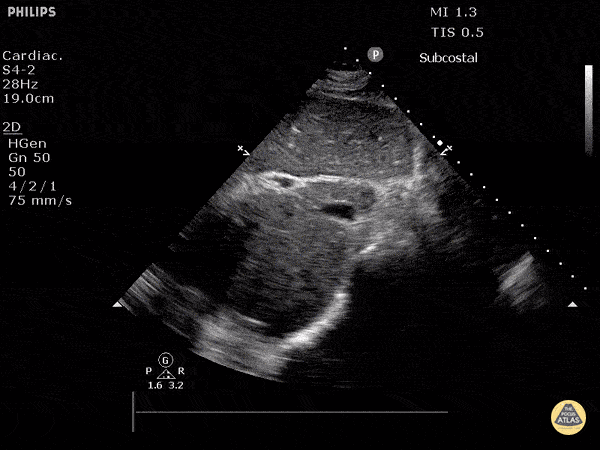

vci-kollaptisch